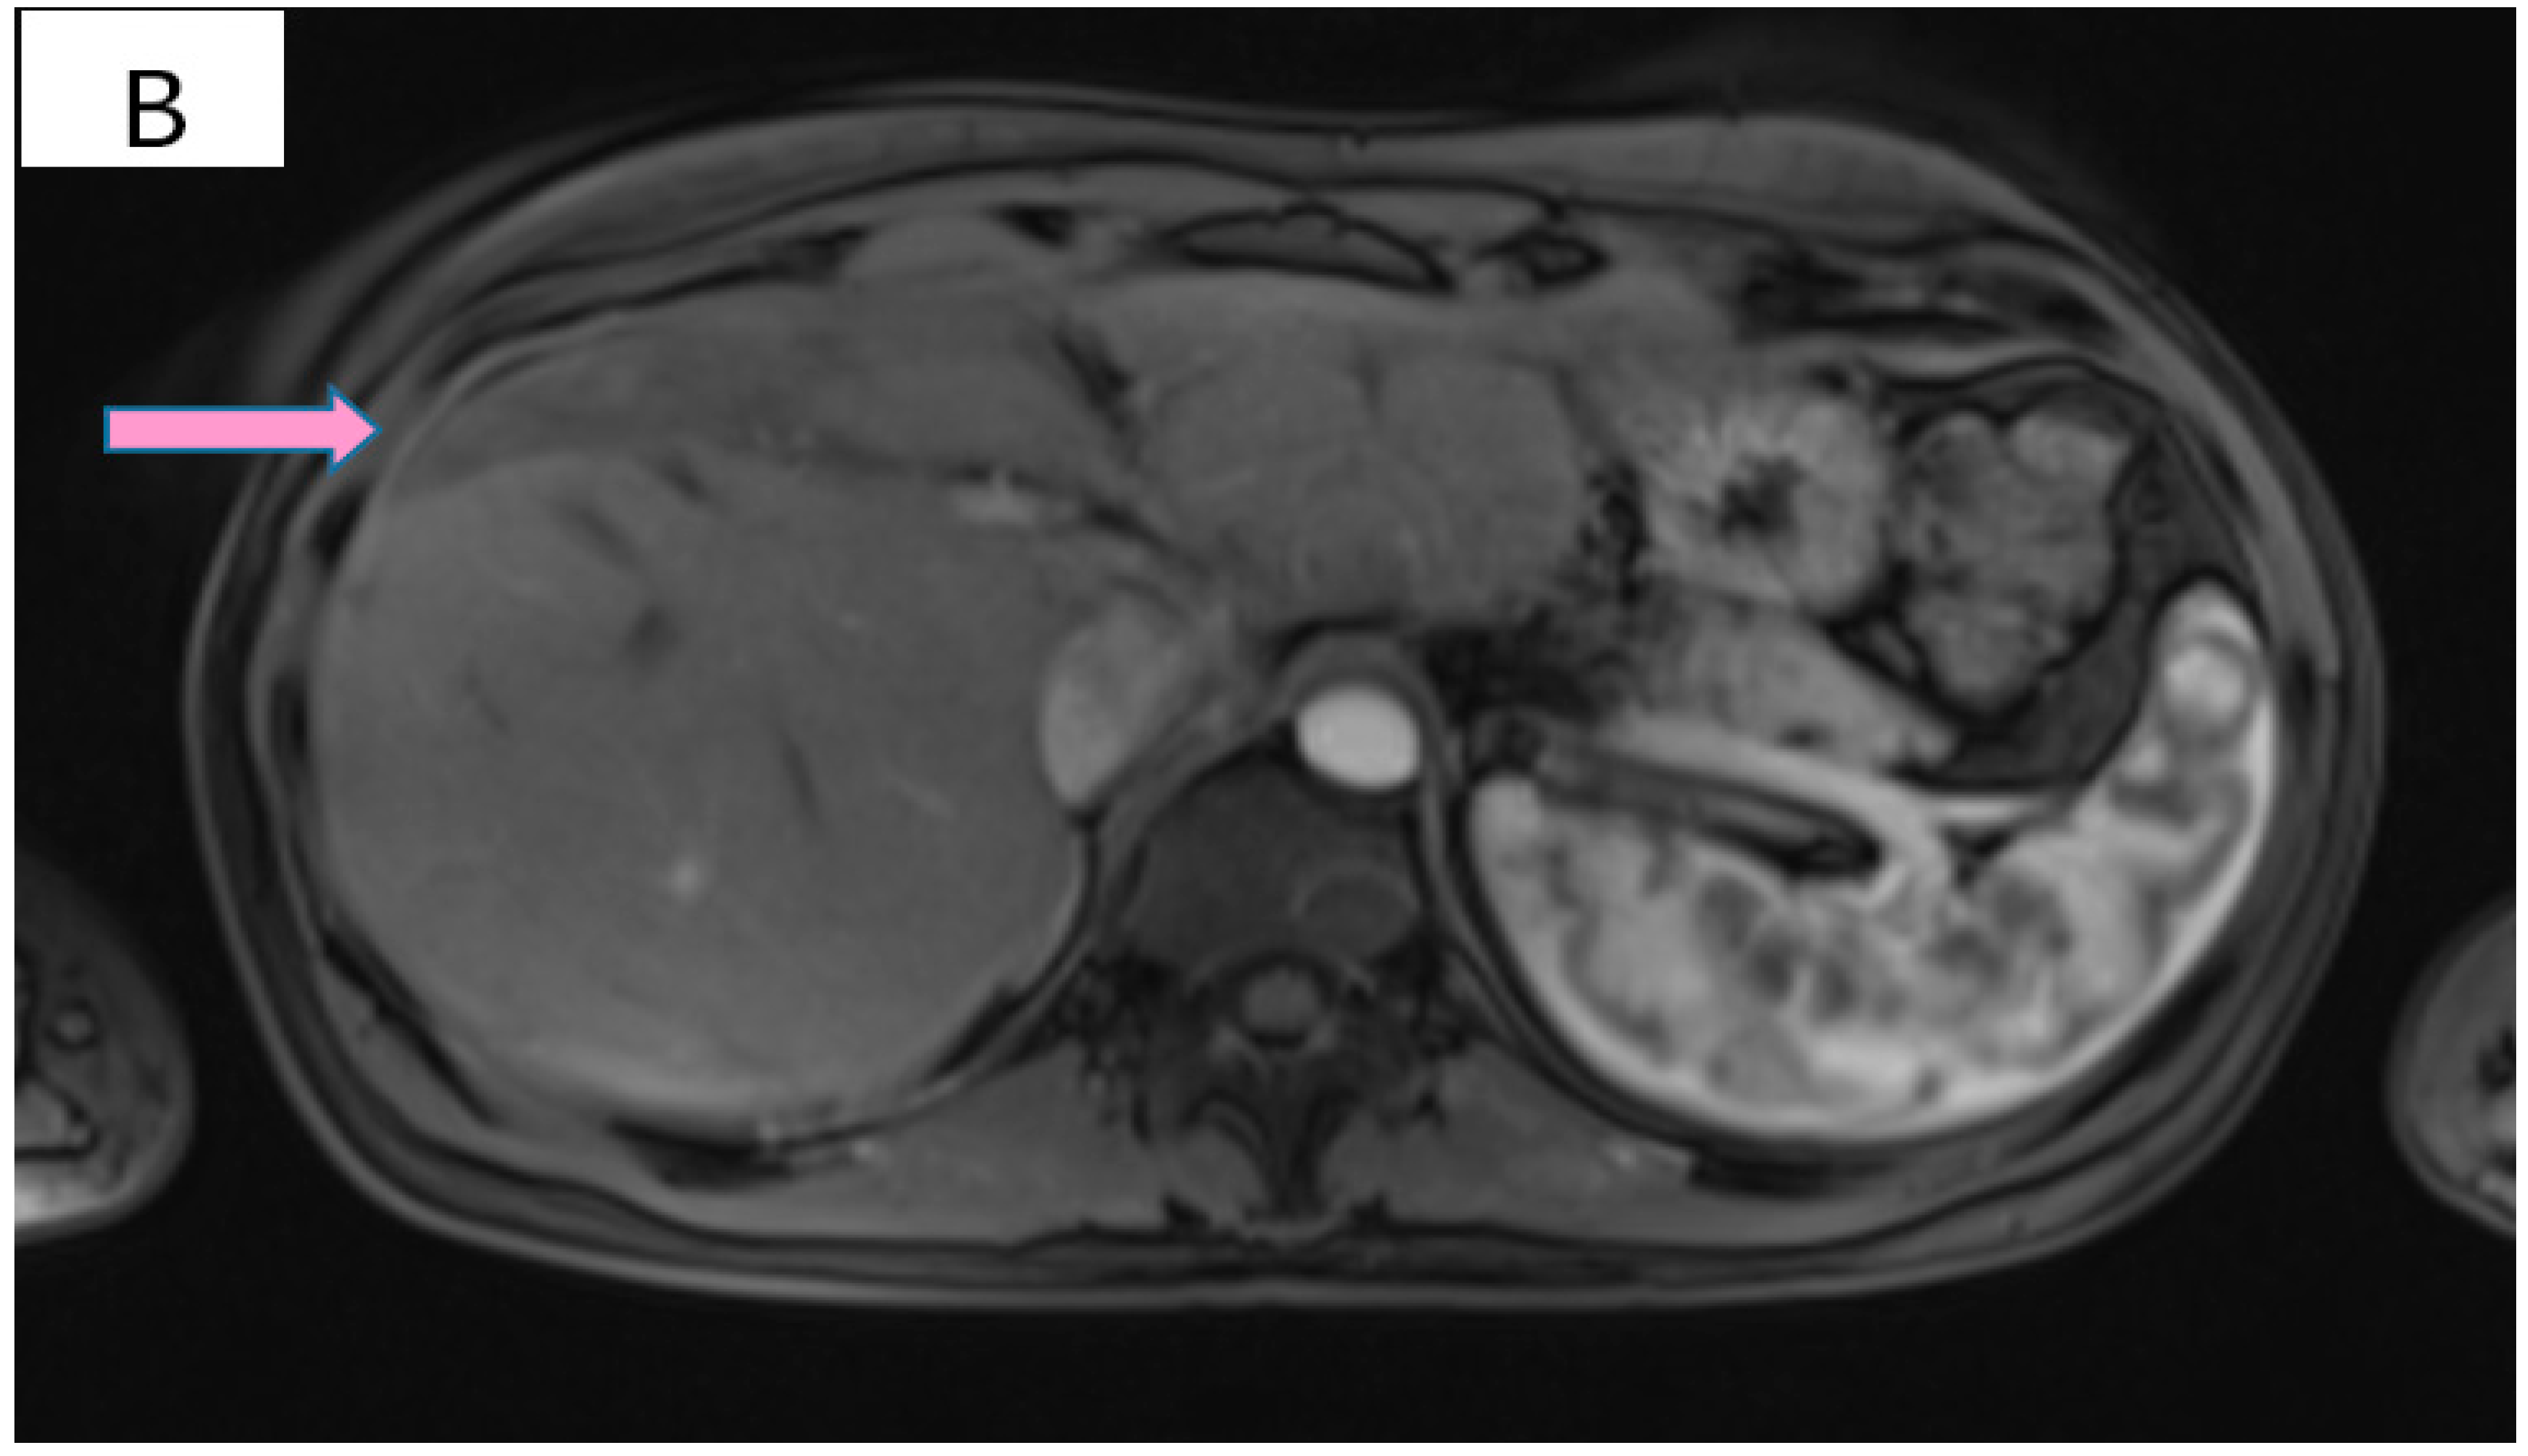

Figure 3.

(A) Pretreatment MRI scan of the abdomen showing a large hypodense mass in the left lobe of the liver—segments VIII and IV (marked by arrows). (B) MRI scan showing a dramatic decrease in size of the metastasis (marked by arrows) in the left lobe of the liver after treatment with six cycles of Pertuzumab, Trastuzumab and Paclitaxel.